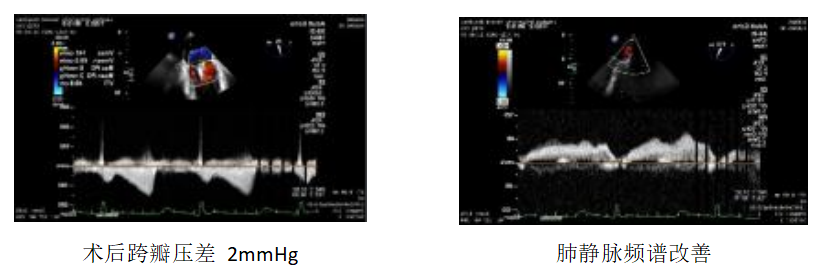

手术中,胡浩教授、张小卫教授团队在TEE引导下, 在房间沟处找到距二尖瓣瓣环平面3.98cm的穿刺位点并成功穿刺,并在超硬导丝引导下,将可操控导引导管置入患者左心房内。术中,胡浩教授、张小卫教授团队再次进行食道超声精细评估后,决定采用 MitraClip TM XTR一枚先在二尖瓣2区进行捕捞和夹持瓣叶,以解决脱垂最严重区位。在大家的密切配合,团队成功将二尖瓣夹成功输送至左心房内,并精准操作将二尖瓣夹定位到 A2 、P2 区病变位置,并顺利完成瓣叶抓捕和夹合,达到预期目标。经TEE观察,XTR内侧仍有部分残余脱垂和少量返流,胡浩教授、张小卫教授团队立即在第一枚XTR夹子内侧再放置一枚NTR,圆满解决了残余脱垂和返流。术后评估显示,患者二尖瓣返流消失,肺静脉频谱明显改善,术后平均跨瓣压差2mmHg,手术圆满成功。